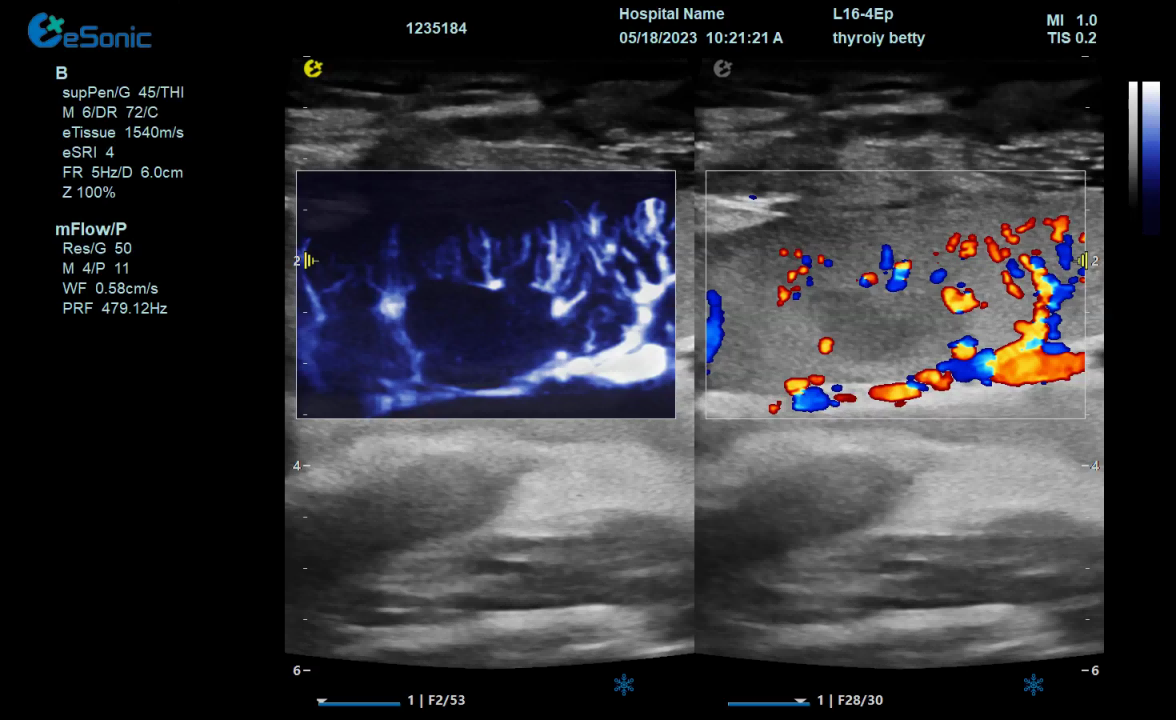

mFlow微血流显像技术,细节分辨率达100μm,支持频谱多普勒及VI血管指数定量。

mFlow无创评估ICU脓毒症患者微循环治疗效果